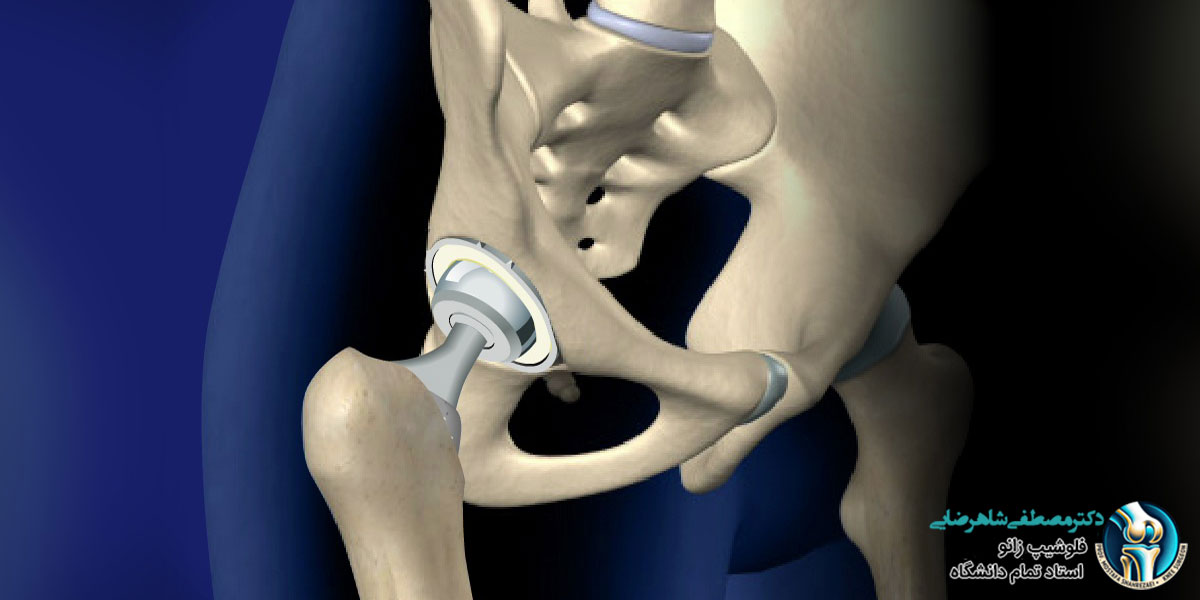

پروتز لگن یک وسیله پزشکی است که جایگزین مفصل لگن آسیب دیده می شود و به افراد کمک می کند تا درد لگن کاهش پیدا کند و راحت تر راه بروند یا فعالیت های روزمره شان را انجام دهند. این پروتزها معمولا برای افرادی استفاده می شوند که به دلیل آرتروز، شکستگی یا آسیب های دیگر مفصل لگن، مشکلات زیادی دارند و حرکت برایشان سخت شده است. یکی از سوالات رایج بیماران، در ارتباط با عمر پروتز لگن است که در ادامه بررسی می کنیم.

انواع پروتز لگن و میزان دوام هر کدام

پروتز لگن انواع مختلفی دارد و هر نوع ویژگی ها و میزان دوام متفاوتی دارد. در ادامه انواع پروتز لگن و میزان دوام تقریبی هر کدام را بررسی می کنیم:

- پروتز سرامیکی: پروتزهای سرامیکی از مواد سخت و مقاوم ساخته شده اند که سطح سایش بسیار کمی دارند و احتمال واکنش های حساسیتی یا التهاب بدن را کم می کنند. این پروتزها دوام بالایی دارند و معمولا بین ۱۵ تا ۲۵ سال یا بیشتر عمر می کنند. با این حال، نسبت به فلز کمی شکننده تر هستند و باید مراقبت بیشتری در فعالیت های شدید ورزشی داشت. برای افرادی که حساسیت دارند یا به دنبال پروتزی با طول عمر بالا هستند، پروتز سرامیکی گزینه مناسبی است.

- پروتز فلزی: این نوع پروتز از فلز ساخته شده و بسیار مقاوم است، به همین دلیل برای افرادی که فعالیت بدنی زیاد دارند یا می خواهند پروتزشان در برابر فشار و ضربه مقاوم باشد مناسب است. دوام آن معمولا حدود ۲۰ تا ۳۰ سال است. با این حال، ممکن است ذرات فلزی ریز در طول زمان آزاد شوند که می تواند باعث التهاب، حساسیت یا مشکلات دیگر در بدن شود.

- پروتز فلز و پلی اتیلن: ترکیب فلز و پلی اتیلن تعادلی بین مقاومت و راحتی ایجاد می کند و دوام آن معمولا ۱۵ تا ۲۰ سال است. فلز بخش مقاوم پروتز را تشکیل می دهد و پلی اتیلن به عنوان سطح ساینده نرم تر عمل می کند تا فشار روی استخوان کم شود. این نوع پروتز بیشتر برای افراد مسن یا کسانی که فعالیت شدید بدنی ندارند توصیه می شود، زیرا پلی اتیلن به مرور زمان ممکن است ساییده شود.

- پروتز سرامیک و پلی اتیلن: این پروتز ترکیبی از مزایای سرامیک و پلی اتیلن را ارائه می دهد. سرامیک باعث کاهش سایش و افزایش دوام می شود و پلی اتیلن راحتی و انعطاف پذیری بیشتری فراهم می کند. معمولا دوام آن بین ۱۵ تا ۳۰ سال است و گزینه ای مناسب برای افرادی است که به دنبال پروتزی با طول عمر بالا و عملکرد راحت هستند. هزینه این نوع پروتز نسبت به دیگر انواع بالاتر است، اما مزایای آن در کاهش سایش و افزایش دوام قابل توجه است.